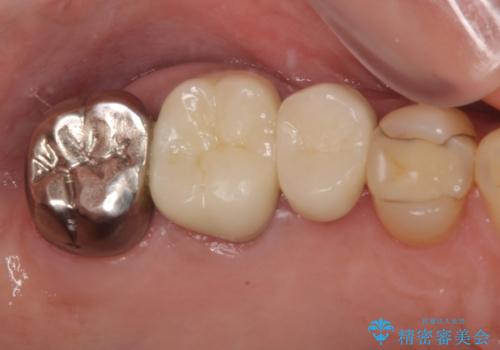

目立つ銀歯と欠けてしまった詰め物 オールセラミッククラウンでの補綴治療